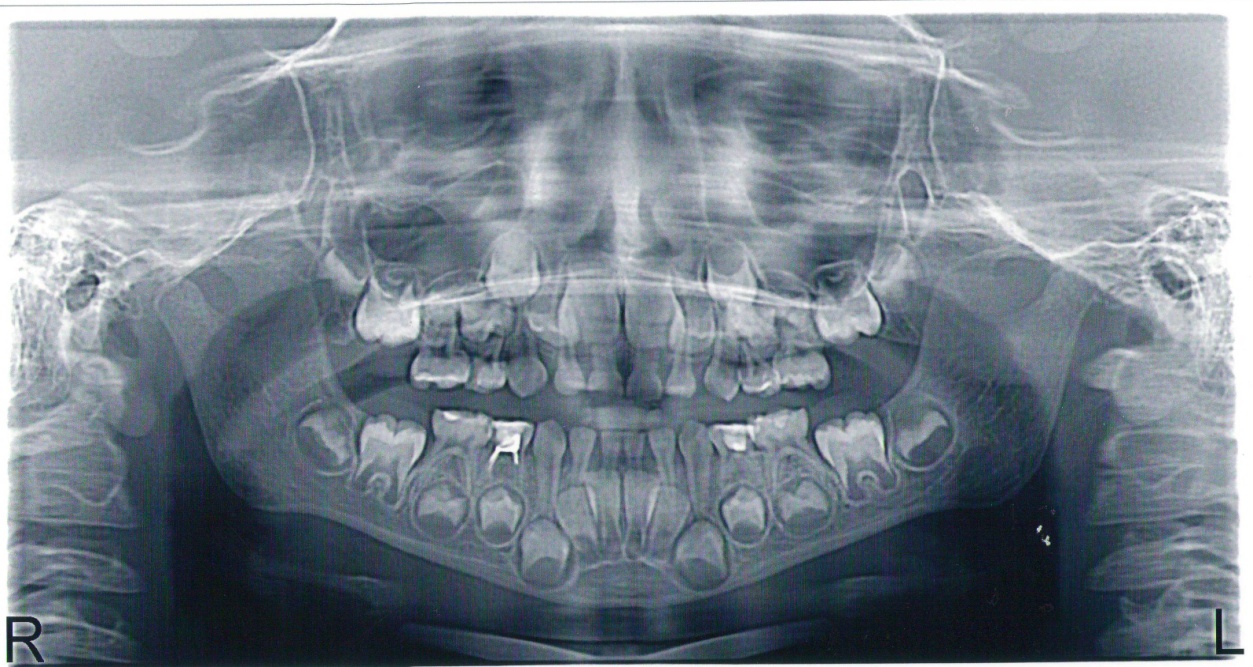

Фотографии и схемы для ОПТГ и мезиального прикуса